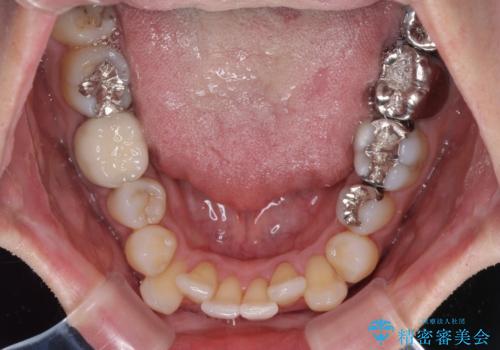

受け口傾向の咬み合わせ 前歯のデコボコをワイヤー矯正で素早く改善

- 前歯の見た目を気にして来院された患者様です。

前歯のクロスバイトは、改善の途中で歯髄壊死を起こすリスクが高くなるため、マウスピース矯正よりもワイヤー矯正をお勧めしております。